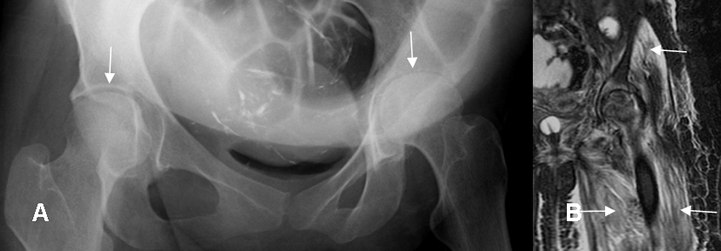

Fig 55. Artritis infecciosa.

A: Rx AP. Disminución del espacio articular en el lado izquierdo, al comparar con el contra-lateral.

B: RM coronal en STIR. Edema óseo en la cabeza femoral y acetábulo, por artritis séptica. Severos cambios inflamatorios en los componentes del cuadriceps y los glúteos, sin formación

de colecciones.

En la fase subaguda hay erosiones óseas e irregularidad de las superficies articulares por destrucción del hueso subcondral y disminución del espacio articular, por daño del cartílago. La aparición de reacción perióstica indica osteomielitis asociada. (20, 21). (Fig 54, 55 y 56).